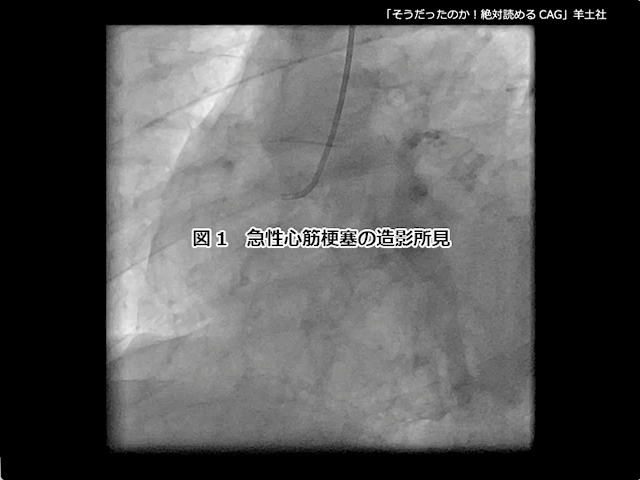

1. 急性冠症候群の造影所見

3. 虚血性心疾患の病態と造影所見

『第5章 虚血性心疾患の病態と冠動脈』より抜粋

第5章-1 急性冠症候群の造影所見